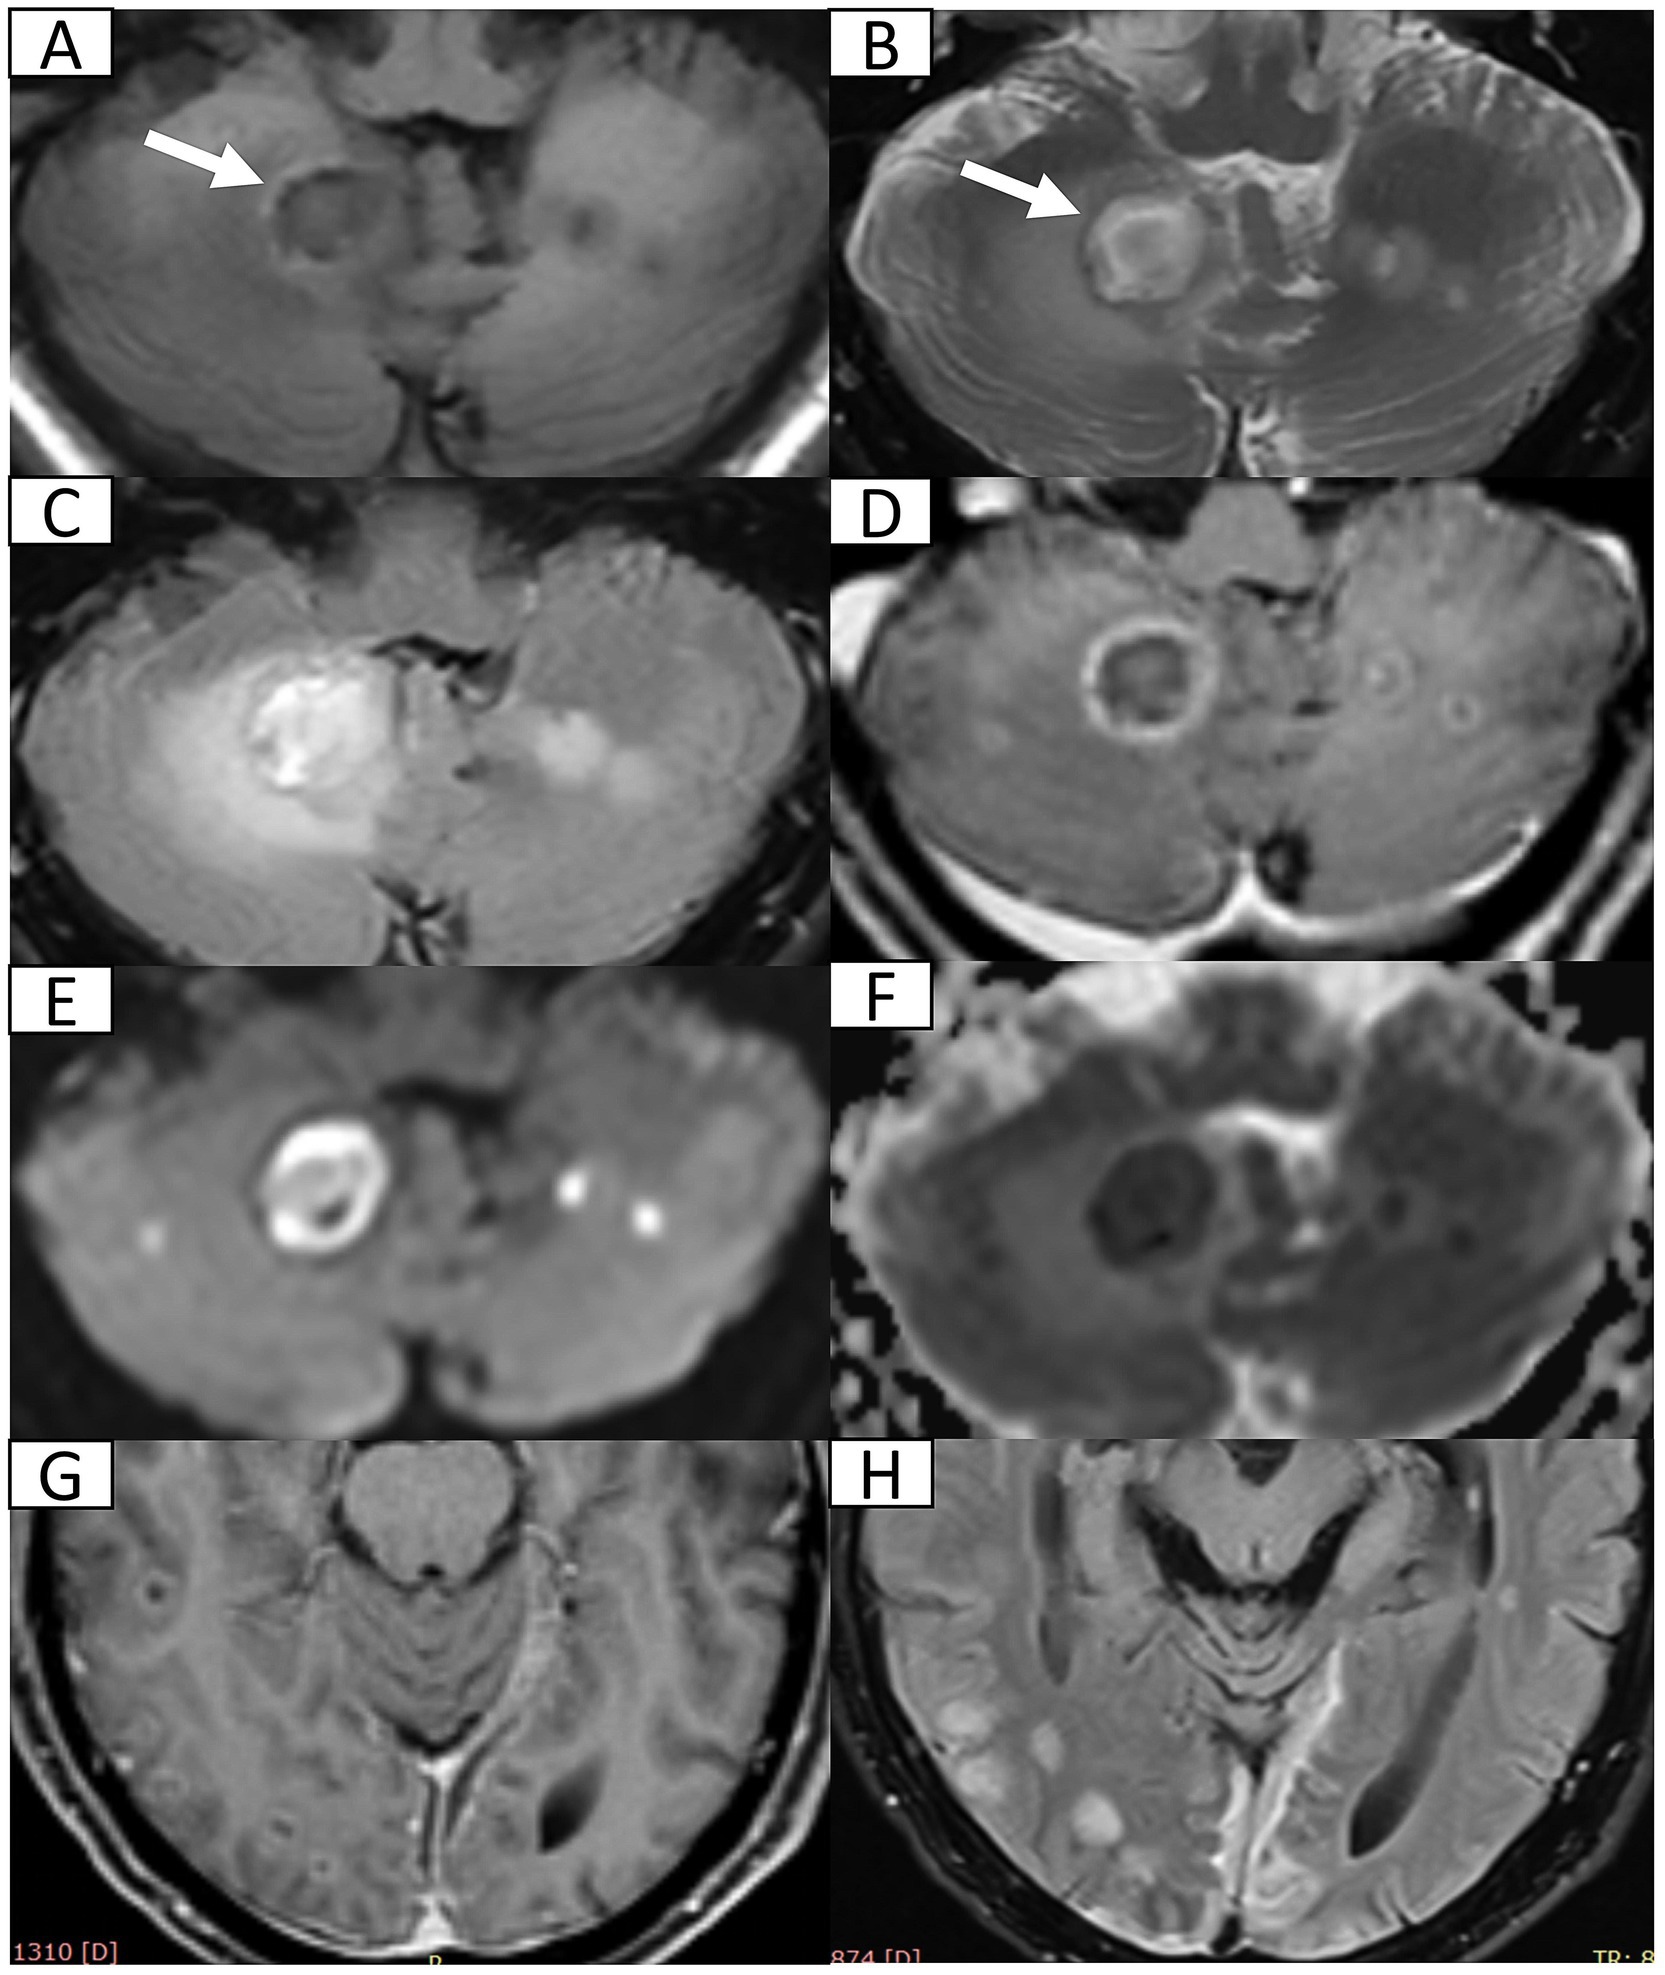

Seven months post-discharge, the patient presented with persistent cognitive-behavioral changes (memory deterioration and personality alteration), marked by disorganized speech, tangentiality, and emotional lability with irritability. Activities of Daily Living preserved without functional impairment, urinary incontinence, dysphagia, or dysarthria. External hospital MRI indicated hydrocephalus, leading to readmission. Neurological exam confirmed isolated cognitive decline without motor, sensory, or cranial nerve deficits. Cognitive assessments showed the Mini-Mental State Examination score of 27/30, Montreal Cognitive Assessment score of 16/30, and Clinical Dementia Rating score of 0.5/3. Lab tests ruled out autoimmune encephalitis, showing normal immunoglobulins (Ig) (IgA, IgG, and IgM) and complement profiles (C3 and C4), and negative antibodies (anti-double-stranded DNA, antinuclear, and extractable nuclear antigen). Apolipoprotein E genotyping demonstrated ε3/ε3 homozygosity. Multimodal 3 T MRI revealed communicating hydrocephalus, hemosiderosis of the right cerebellar hemisphere, and a patchy hyperintensity on T2-weighted imaging of the left anterior medulla oblongata (Figures 2AG). Lumbar drainage and gait assessment excluded normal pressure hydrocephalus. Differential diagnoses also excluded medullary infarction (absence of diffusion restriction on DWI) and amyotrophic lateral sclerosis (atypical topography). The final diagnosis was secondary hydrocephalus with cerebellar hemorrhage sequelae and HOD. Management included symptomatic support, i.e., glycemic control (glibenclamide 30 mg qd and acarbose 50 mg q8h) and antihypertensives (nifedipine 30 mg qd and amlodipine 5 mg qd). Post-intervention symptom relief was achieved. The patient was discharged with cognitive symptom management and ongoing glycemic and hypertensive control. At 5-month follow-up, head 3 T MRI confirmed persistent lesions (Figures 2H,I) without symptom progression or cognitive deterioration. The timeline of clinical events is summarized in Figure 3.

Figure 2

Figure 2. Head 3 T MRI after second admission and at 5-month follow-up. (A,B) Axial T2-weighted imaging (T2WI) and fluid-attenuated inversion recovery (FLAIR) sequence reveal focal hyperintensity and mild hypertrophy in the left anteromedullary bulbar region (arrow) indicating secondary olivary degeneration. (C,D) Axial diffusion weighted imaging and corresponding apparent diffusion coefficient map show normal diffusion within lesion (arrow) excluding acute ischemia or abscess recurrence. (E) Axial T2WI at the cerebellopontine level depicts patchy hypointensity in the right dentate nucleus (arrow). (F) Axial susceptibility-weighted imaging (SWI) confirms hemosiderosis in the right dentate nucleus. (G) Three-dimensional reconstruction of diffusion tensor imaging, via syngo. MR Neuro 3D (Siemens, Erlangen, Germany), reveals marked fiber tract disruption in the left olivary nucleus consistent with transsynaptic degeneration. (H) FLAIR sequence reveals persistent T2 hyperintensity in enlarged left anteromedullary bulbar (arrow). (I) SWI demonstrates persistent hypointensity in the right dentate nucleus (arrow) suggestive of hemosiderin deposition.